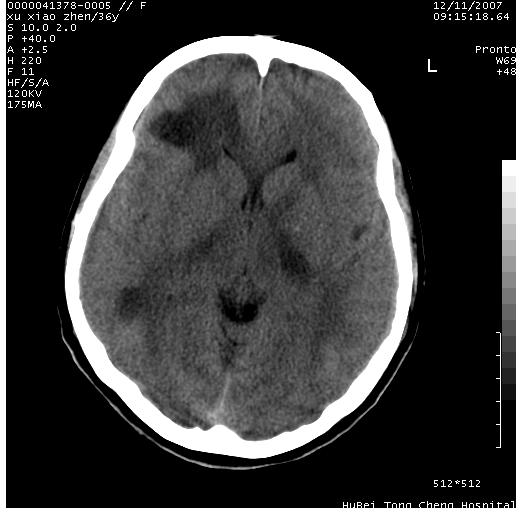

以下是引用wzr在2007-12-12 18:58:00的发言:[br]以脑白质受累,脑肿胀明显,脑室变窄,多考虑炎性改变,建议进一步ce或mri明确.

以下是引用wqs571018在2007-12-12 19:48:00的发言:[br]脑白质受累,脑肿胀明显,脑室变窄,多考虑炎性改变,脑膜炎可能性大;建议mri明确.。